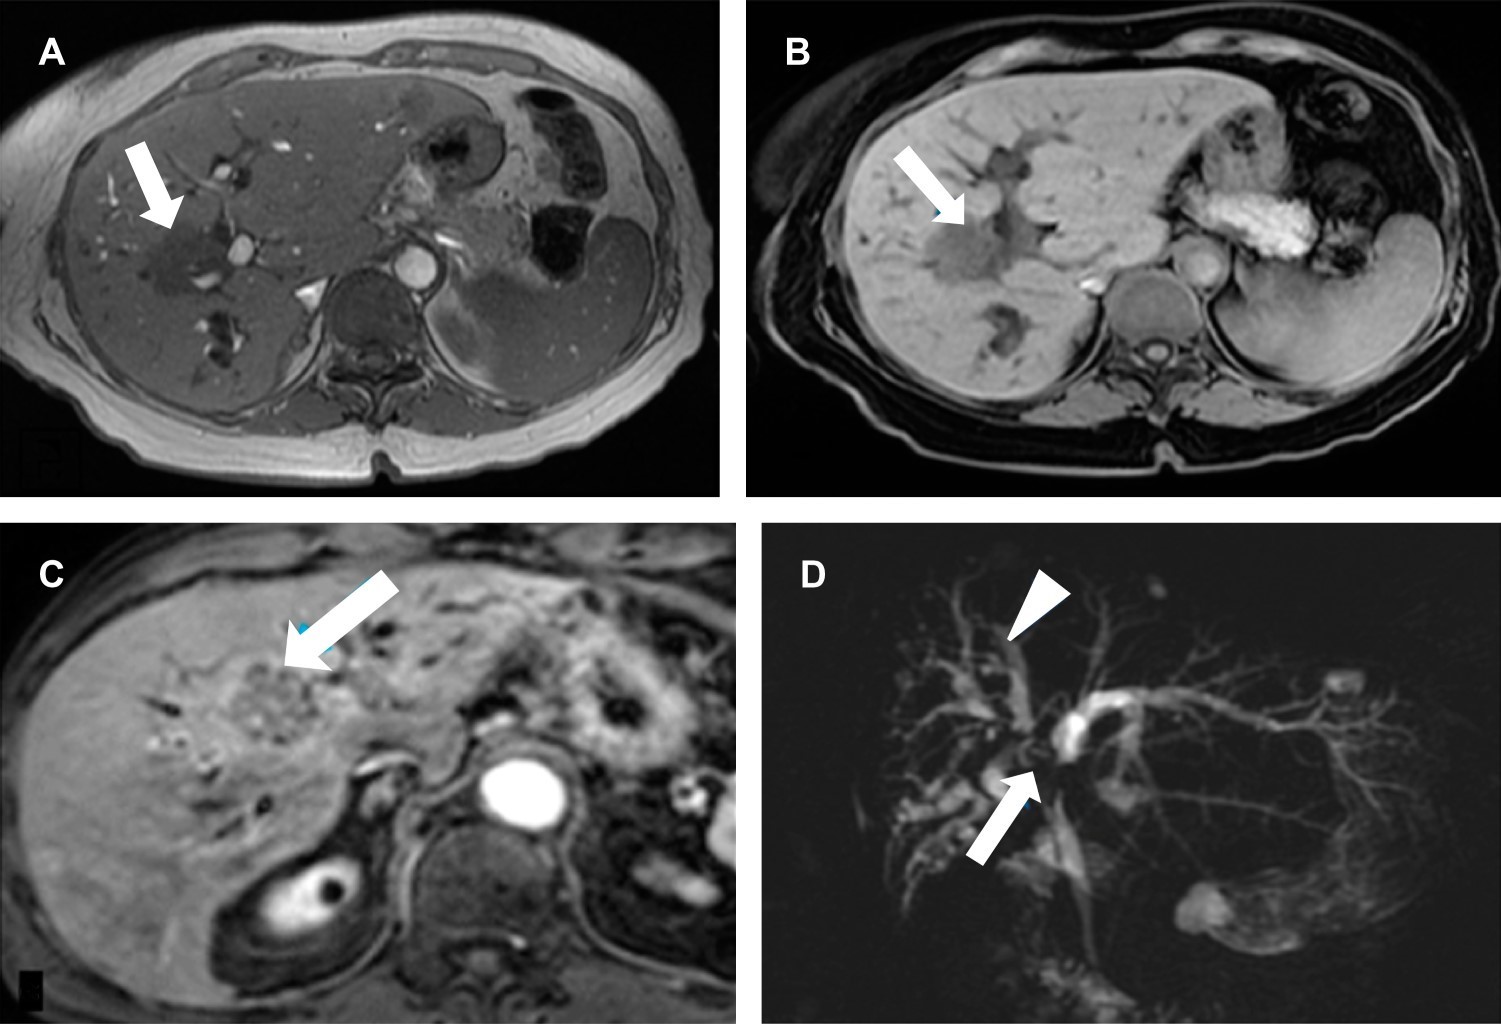

Cholangiocarcinoma is a neoplasm of the bile duct epithelium. Its frequency of appearance is low despite being the second most common primary liver cancer in the world (incidence 2%). Predominates in men have a poor prognosis and high mortality; survival in early stages is 40 months with surgery and 12 with advanced-stage chemotherapy. The low symptoms specificity at the presentation and local tumor infiltration at the time of diagnosis usually prevent the possibility of radical surgical resection. Suspicion of cholangiocarcinoma is based on signs of biliary obstruction and elevation of tumor markers (Ca 19-9). We will refer to a patient with cholangiocarcinoma of the hilar confluence (Klatskin tumor) and the magnetic resonance findings.

Figure 2